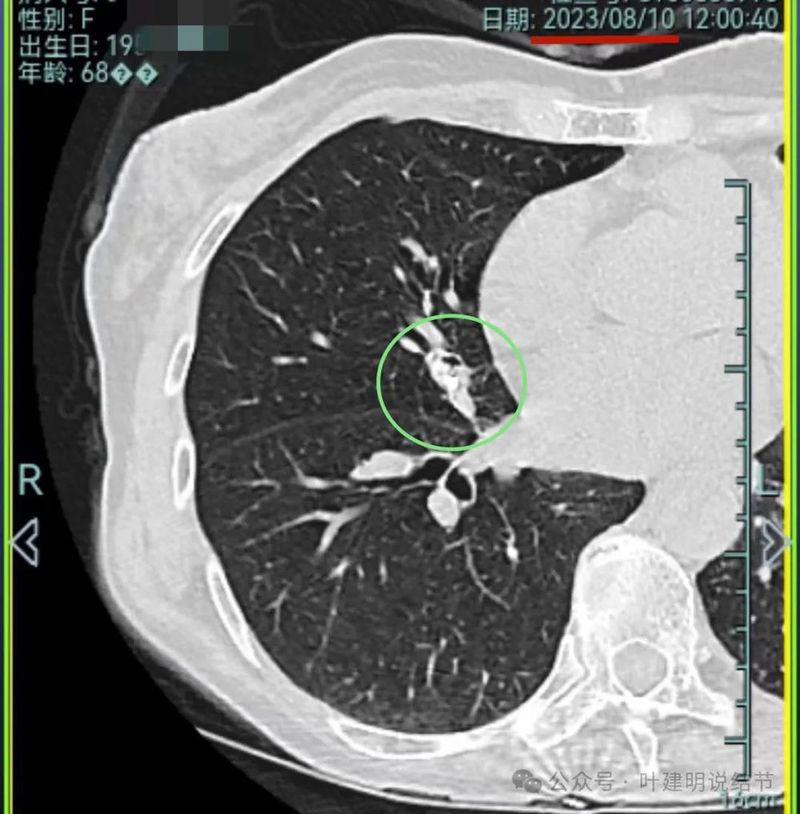

再看2023年8月的影像:

病灶1没什么进展。

病灶2与前相仿。

病灶3仍混合密度,说不上显著进展。

病灶4 仍是钙化的,大小也没有进展。

病灶5较前密度又有增高,贴着叶间裂,整体轮廓显得较之前清楚些,更符合恶性表现了,而且应该是浸润性腺癌。

病灶6与前相仿。